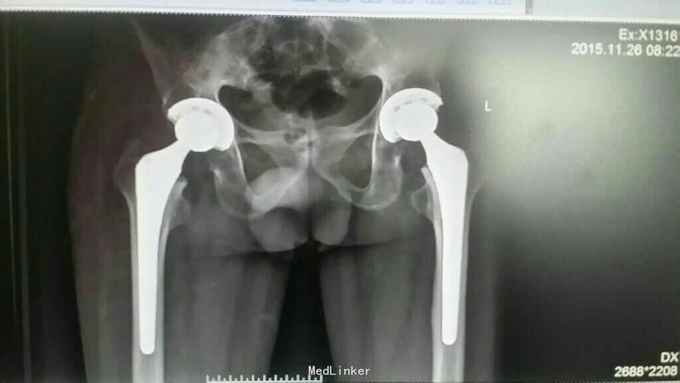

患者术后经过正规康复锻炼,髋关节疼痛症状消失,双髋关节屈伸活动范围达80度,髋关节屈曲畸形得到矫正,术后生活可以自理,可以处理正常家务劳动。 我们常规后外侧入路行髋关节置换手术,各位老师们不知有无选择此切口实行强直性髋关节置换?有什么更好的经验可以留言,谢谢!